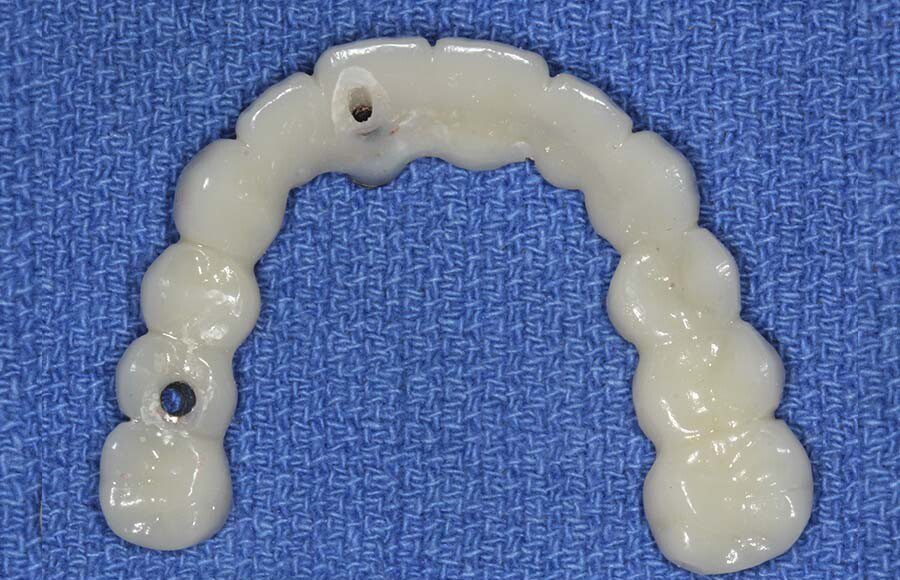

Smile GalleryImplant RestorationsFull Mouth Implant Restoration Full arch zirconia implant bridge (full smile) 1 of 37 Pre-op full smile Pre-op lips retracted Pre-op panoramic x-ray Extraction of strategic teeth Placement of implants Extraction of some remaining teeth after verification of adequate implant stability Occlusal view Post-op panoramic x-ray Immediately fabricated provisional restoration (tissue side view) Immediately fabricated provisional restoration (occlusal side view) Immediate provisional delivered on day of surgery Immediate provisional 2 weeks later Scalloped tissue developed from the provisional at 2 weeks Jig used for making a master impression Provisional in place (full smile) Provisional in place (lips retracted) Provisional in place (right side) Provisional in place (left side) Wax try-in (full smile) Wax try-in (right side full smile) Wax try-in (left side full smile) Wax try-in (full face, lips together) Wax try-in (full smile) Wax try-in (right side) Wax try-in (left side) Wax try-in (lips retracted) Full arch zirconia implant bridge on master cast (frontal view) Full arch zirconia implant bridge on master cast (occlusal view) Implant positions and soft tissue representation on master cast (occlusal view) Soft tissue representation on master cast (frontal view) Full arch zirconia implant bridge (tissue side view) Soft tissues on day of delivery (occlusal view) Soft tissues on day of delivery (frontal view) Full arch zirconia implant bridge delivered (lips retracted) Full arch zirconia implant bridge (lips retracted, close up) Post treatment panoramic x-ray Full arch zirconia implant bridge (full smile)